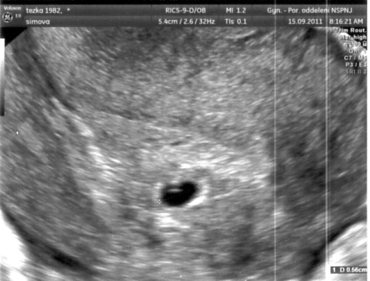

Tak takhle to maličké vypadá, když je úplně maluškaté...

...móóc hezké Yashi, sice ještě maličké, ale krásné...

A to je ta bílá tečička v tom černém? Já vždy viděla až trošku větší, kde už byly vidět ty pupence nožiček a ručiček....To je sranda!!! Tedy s prominutím. To je velikánské štěstí...Ale i sranda, jak se člověk dívá na své budoucí dítě, které se s ním jednou bude hádat, že chce zůstat s kámošema venku dýl.....a odmlouvat a zlobit a smát se, a objímat maminku.....a zatím ten budoucí člověk je takovou malinkou tečičkou. Úžasný. Chci taky tečičku!!!!

holky, jojo, je to ta bílá fazolka v té černém fleku :-) lucy, jak říkáš, sranda :-)